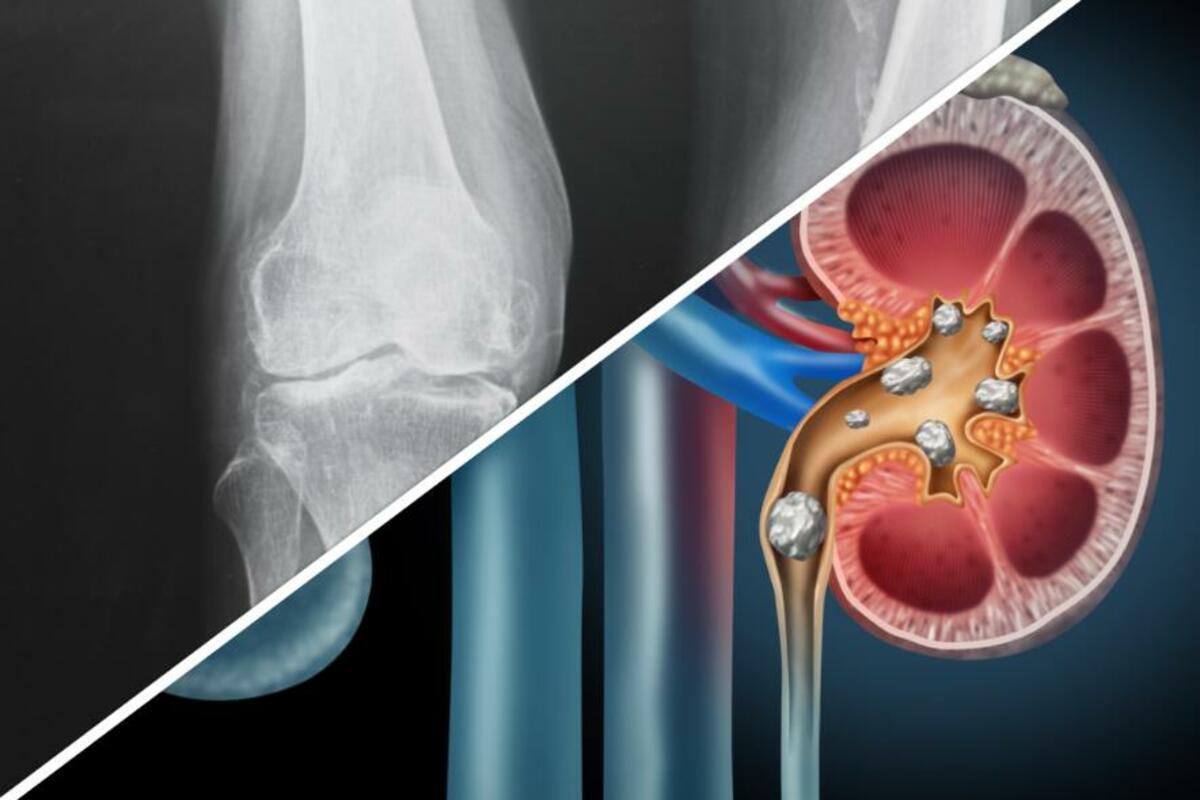

U zglobovima i tetivama

Kad se kalcijum nataloži u zglobovima i tetivama, nastaje stanje koje se naziva kalcificirajući tendinitis. To stanje često zahvata tetive rotatorne manžete, a jedan je od glavnih uzroka bolova u ramenu. Kalcificirajući tendinitis najčešće pogađa osobe između 30 i 50 godina i češći je kod žena nego kod muškaraca. Uzrok još nije potpuno razjašnjen, ali smatra se da bi rizični faktori mogli da budu neka druga medicinska stanja poput gihta, dijabetesa, endokrinih bolesti, smrznutog ramena ili puknuća rotatorne manžete. Kalcifikati u ramenima mogu izazvati bol i neprijatnost pri pokretima ramena te dovesti do smanjenja opsega pokreta, ali ponekad ne izazivaju nikakve simptome, već se otkrivaju slučajno na rendgenskim snimcima rađenim zbog nekog drugog problema.